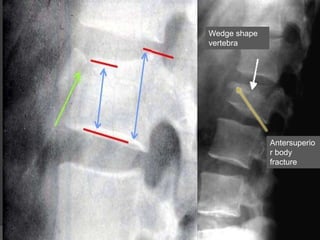

Wedge fracture

 Compression

fracture resulting from

flexion.

Flexion compression injury

 Best seen on lateral view

 Stable

 Common in

 Elderly patients

with osteoporosis or osteogenesis

imperfecta

Wedge shape

vertebra

Antersuperio

r body

fracture